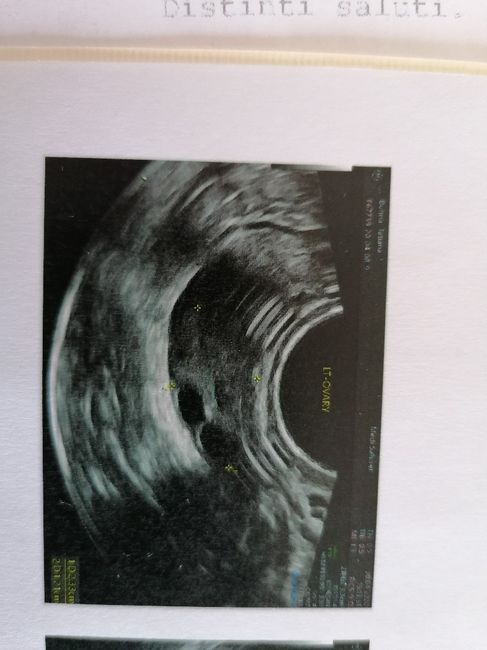

Buongiorno a tutte e buona pasquetta, qualcuna che ha fatto monitoraggio per l'ovulazione mi sa dire se secondo lei con questa eco ero vicina all'ovulazione? Eco fatta a 5 pm.Oggi sono a 10 pm.

Ciao ragazze, qualcuna che ha fatto monitoraggi durante l'ovulazione. 2 giorni fa ho fatto l'eco a 6 pm, ciclo post biochimica. Vedendo l'ecco mi sembra vicino alla fase ovulatoria, su indo voi?